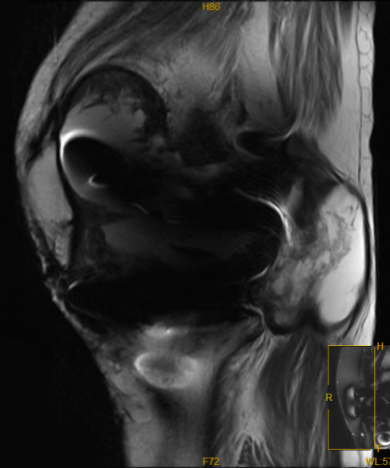

▲ MRI提示:滑膜组织增生,关节腔积液,囊肿形成